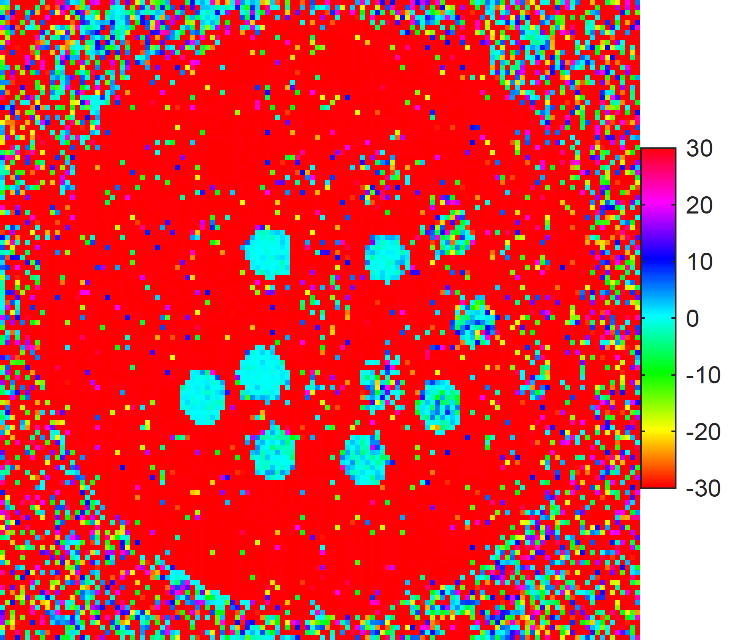

4.3 Verification of TEUSQA with prospective acquisition

Figure 8 shows the difference in estimated T1subscript𝑇1T_{1} and T2subscript𝑇2T_{2} maps for the test and retest acquisition. We select the spheres where the nominal T1subscript𝑇1T_{1} and T2subscript𝑇2T_{2} values are expected to be mapped correctly by the sequence settings. In these spheres the mean difference between maps from test and retest is close to zero. Outside of these spheres large differences can be observed. The bias in the T1subscript𝑇1T_{1} and T2subscript𝑇2T_{2} estimates compared to the nominal values was on average about 5%percent55\% and 28%percent2828\% respectively in the selected spheres. A detailed comparison with the nominal values is presented in the figures 6 and 7. Following this we computed ηpACQsubscriptsuperscript𝜂𝐴𝐶𝑄𝑝\eta^{ACQ}_{p} over the selected spheres which was found to be 0.2210.2210.221 with 95%percent9595\% confidence bounds [0.201,0.241]0.2010.241[0.201,0.241] for T1subscript𝑇1T_{1} and 0.1220.1220.122 with [0.111,0.134]0.1110.134[0.111,0.134] 95%percent9595\% confidence bounds for T2subscript𝑇2T_{2}. The predicted ηpsubscript𝜂𝑝\eta_{p} for T1subscript𝑇1T_{1} and T2subscript𝑇2T_{2} were 0.2540.2540.254 and 0.1250.1250.125, respectively. The predicted ηpsubscript𝜂𝑝\eta_{p} for T1subscript𝑇1T_{1} was within 12%percent1212\% of the observed ηpACQsubscriptsuperscript𝜂𝐴𝐶𝑄𝑝\eta^{ACQ}_{p} while for T2subscript𝑇2T_{2} it was within the 95%percent9595\% confidence bounds of observed ηpACQsubscriptsuperscript𝜂𝐴𝐶𝑄𝑝\eta^{ACQ}_{p}.

Refer to caption

(a) T1subscript𝑇1T_{1} difference map from T1subscript𝑇1T_{1} array

(b) T2subscript𝑇2T_{2} difference map from T1subscript𝑇1T_{1} array

(c) T1subscript𝑇1T_{1} difference map from T2subscript𝑇2T_{2} array

(d) T2subscript𝑇2T_{2} difference map from T2subscript𝑇2T_{2} array

Fig. 8: Test-retest difference maps for T1subscript𝑇1T_{1} (left) and T2subscript𝑇2T_{2} (right) estimates in the T1subscript𝑇1T_{1} (top) and T2subscript𝑇2T_{2} array (bottom) of the ISMRM model 130 phantom [22] (units in ms). Scans were made using prospective undersampling using the Halton pattern with acceleration factor R=32𝑅32R=32.